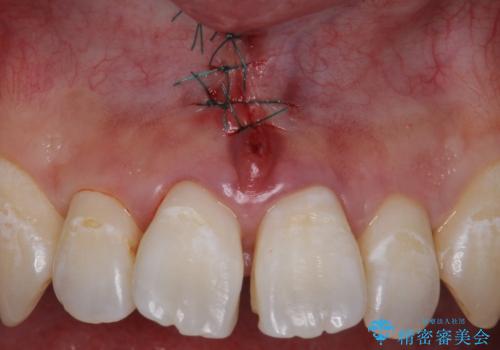

上唇小帯の切除

- 矯正治療の検査時に上唇小帯が短いことがわかり、矯正後の後戻りの予防目的で上唇小帯の切除を行いました。

上の前歯の歯と歯の間にすき間がある場合は、上唇小帯のついている位置やその長さが原因となっている場合があります。

そのままにしておくと矯正中に前歯のすき間が閉じきらなかったり、閉じたとしても後戻りをしてまたすき間ができてしまう可能性があります。

矯正の予定がなくとも、上唇小帯のつく位置が歯に近いと清掃性が悪くなるため手術で改善することをおすすめします。

- 外科手術のため、術後に出血、痛みや腫れ、違和感を伴います